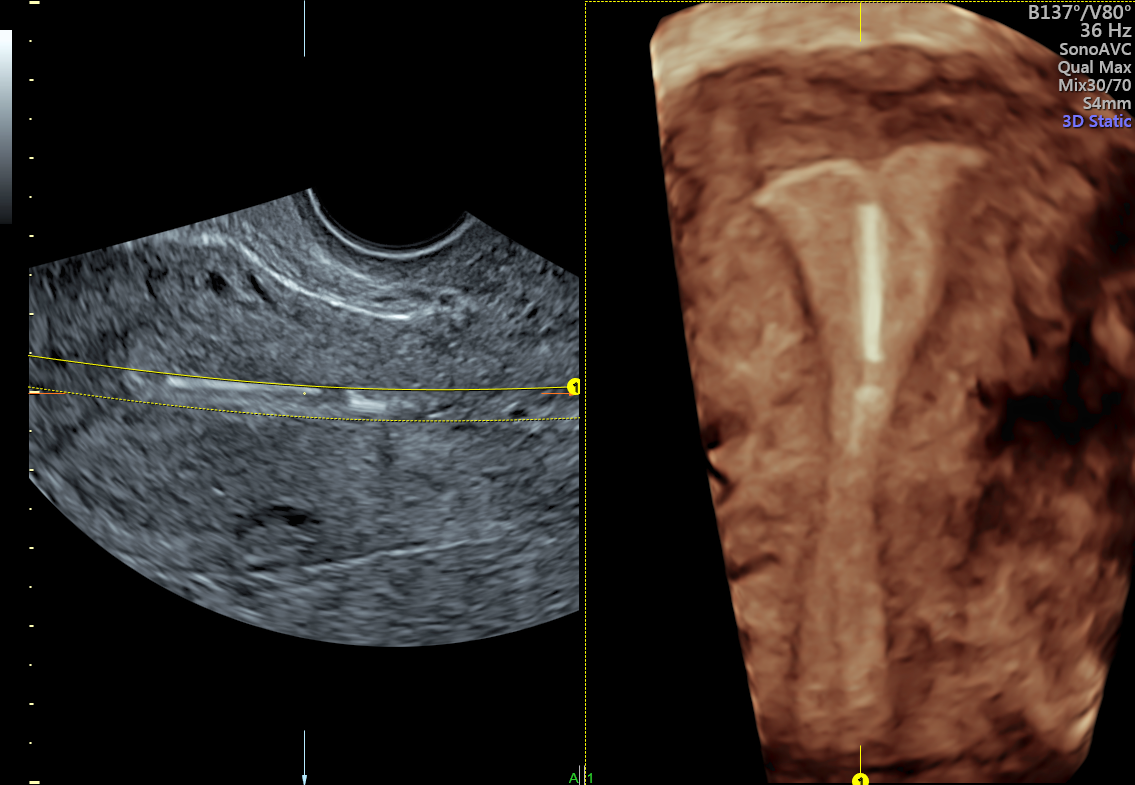

Assessing Malpositioned IUD Symptoms With 3D Ultrasound Empowered

From www.volusonclub.net

Assessing Malpositioned IUD Symptoms With 3D Ultrasound Empowered Are 3D Ultrasounds Dangerous in other words, 3d sonograms and 4d ultrasounds are not part of routine prenatal exams. if your doctor deems a 3d or 4d ultrasound necessary, there's no cause for concern. Ultrasounds have moved beyond the grainy, indecipherable images of the past. are 3d ultrasounds safe? in most cases, 3d ultrasounds are elective. yes, 3d ultrasound is. Are 3D Ultrasounds Dangerous.